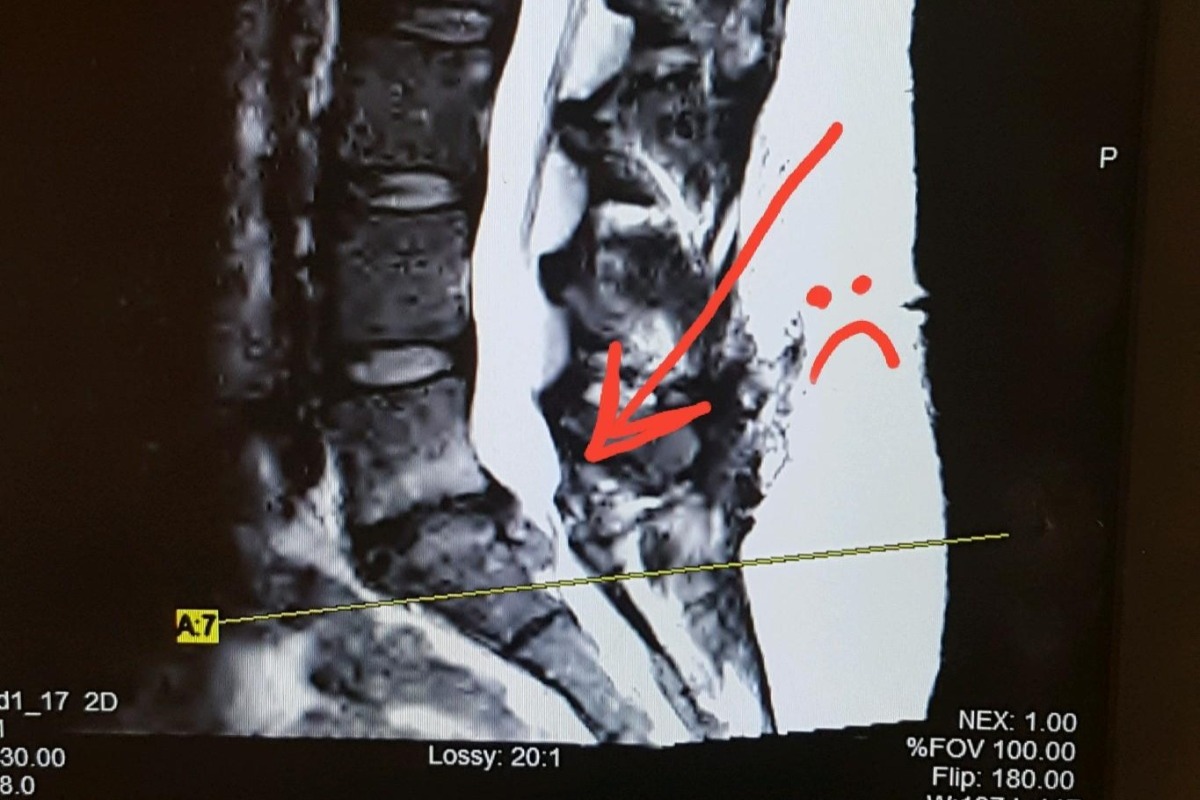

I decided to set up this page to help out Aisha through this tough time. As many of you know Aisha has just had her second unexpected, and unplanned emergency spinal surgery in a year and a half. This operation was a little more intense because the doctor had to go through scar tissue from the initial surgery. Although she has health insurance, her copay is actually $6,000! She used up all of her savings from her first spinal microdiscectomy followed closely by the broken foot.

As you can imagine, the hardship on her family is exacerbated by the fact that she can't work for at least 6 weeks. She REALLY needs to take this time to heal correctly and CAN'T rush back to work because she needs to avoid a potential fusion of her L5/S1 disc. I want to take as much stress off of her as possible so she can allow her body to fully heal. She is self-employed and this is her busiest month of the year, which is adding to her stress that we can help alleviate.

I decided to set up this page to help out Aisha through this tough time. As many of you know Aisha has just had her second unexpected, and unplanned emergency spinal surgery in a year and a half. This operation was a little more intense because the doctor had to go through scar tissue from the initial surgery. Although she has health insurance, her copay is actually $6,000! She used up all of her savings from her first spinal microdiscectomy followed closely by the broken foot.

As you can imagine, the hardship on her family is exacerbated by the fact that she can't work for at least 6 weeks. She REALLY needs to take this time to heal correctly and CAN'T rush back to work because she needs to avoid a potential fusion of her L5/S1 disc. I want to take as much stress off of her as possible so she can allow her body to fully heal. She is self-employed and this is her busiest month of the year, which is adding to her stress that we can help alleviate.